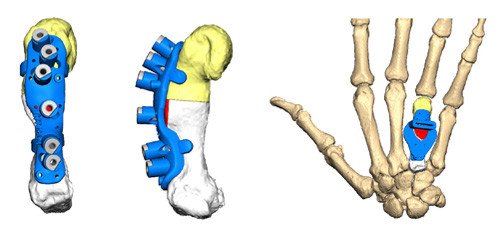

Korrektur eines fehlverheilten Mittelhandknochens mit starker Verkürzung

Neue Verfahren mittels digitaler Computer-Simulation lassen uns anhand der gesunden Gegenseite am Computer die Operation und Korrektur der betroffenen kranken Seite simulieren und somit präzise die Operation im Vorfeld planen. Spezifische im 3D-Drucker gedruckte und dann sterilisierte Schnittlehren («Schablonen») helfen uns, während der Operation die simulierte Operation exakt durchzuführen. Die präzise Korrektur anhand der gesunden Gegenseite kommt bei diesen komplexen Eingriffen dem Patienten und auch dem beteiligten OP-Team entgegen.

Nach erfolgter Korrektur des betroffenen Knochens oder Gelenkes fixieren wir diese in korrekter anatomischer Stellung mit Platten und Schrauben. Im Einzelfall werden diese Platten individuell auf die persönliche Anatomie des Patienten angepasst und sogar mit spezifischen 3D-Druckern als Titanimplantat individuell hergestellt. Unsere Abteilung hat als Mitentwickler dieses Verfahren bereits langjährige Erfahrung und somit entsprechende Expertise (erster Eingriff mit solch einem Verfahren im Jahr 2016). Welches operative Verfahren angewendet wird, wird im Einzelfall individuell besprochen und geplant.